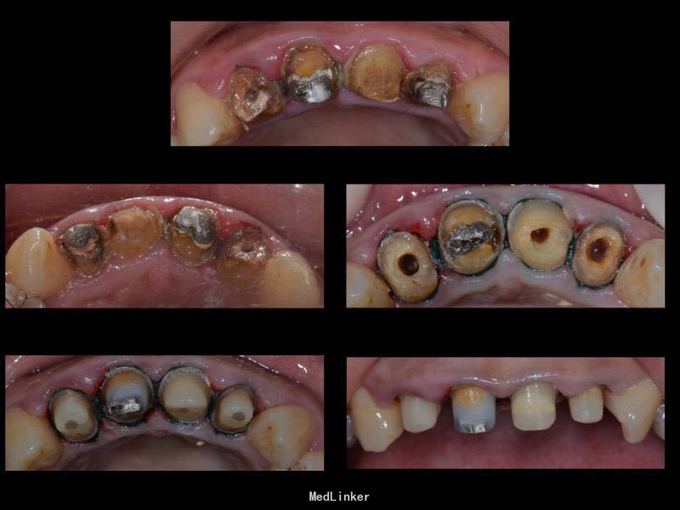

上门牙外伤金属烤瓷冠修复七年,牙龈发黑,红肿,有异味,颜色黄不美观,其他牙也黄不美观,要求重新修复

11 12 21 22金属烤瓷冠修复,牙龈发黑,冠颈部牙龈萎缩红肿有黑褐色腐质物,探出血,叩(-).23近中颊侧扭转倾斜.36 37 46 47残根,松动轻,全口牙结石中度,牙齿颜色偏黄,全景片示,11 12 21 22根管治疗不完善,根尖低密度影,有金属桩修复

11 12 21 22死髓牙,不良修复体,牙龈炎 36 37 46 47残根 牙列不齐 处置:全口洁治。 比色,拍照,取模型做蜡型。 拆除旧修复体,拆桩核,做根管治疗,纤维桩修复,牙体预备,取模,做临时冠,粘固。11 12 21 22全瓷冠修复,13 14 23 24 31 32 33 34 41 42 43 44瓷贴面修复。